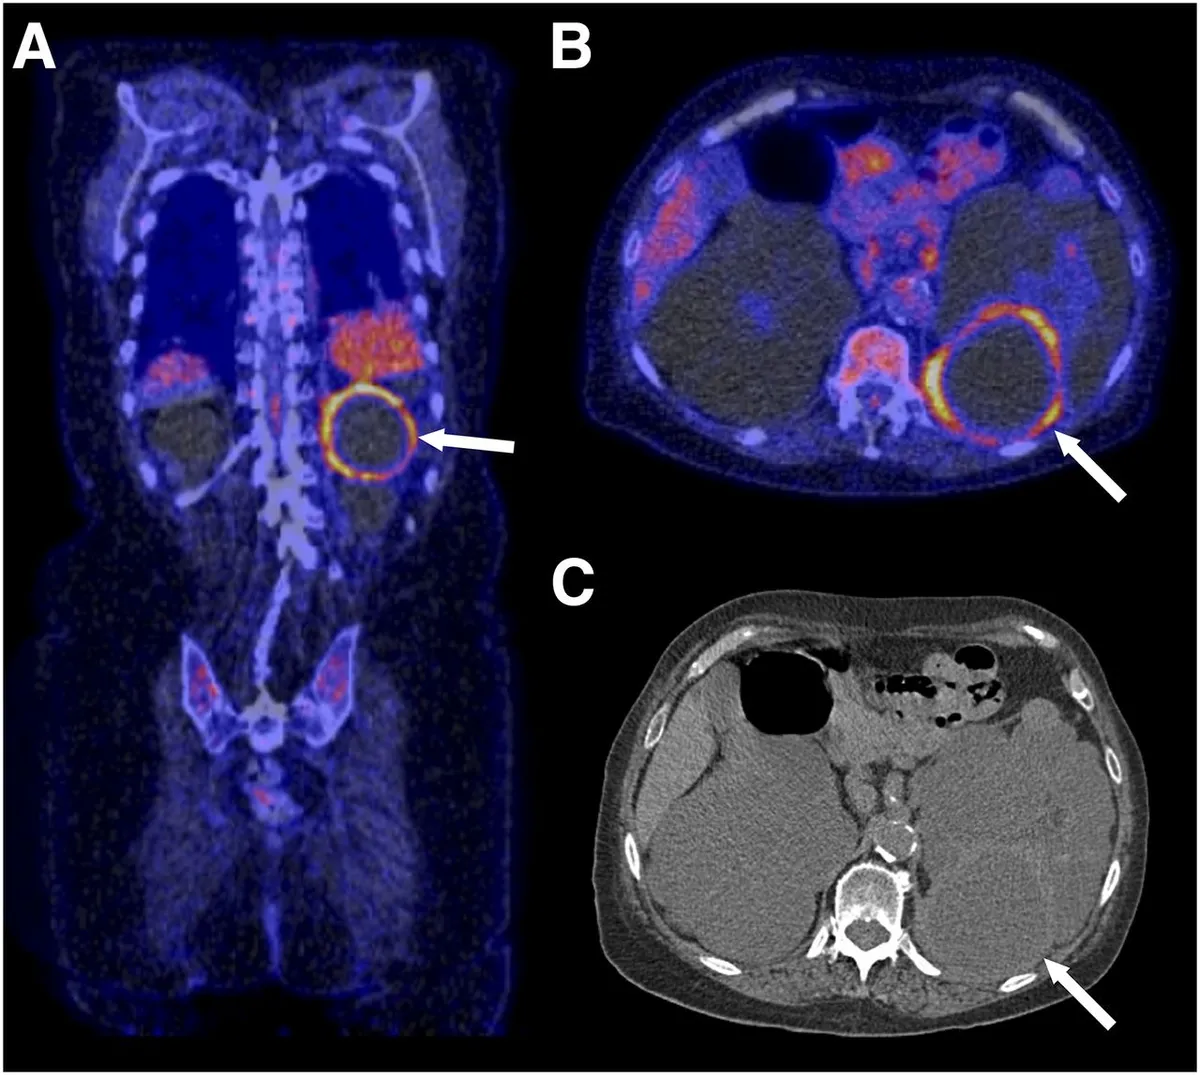

Intoxicação por citrato na contínua: quando suspeitar e como tratar

Intoxicação por citrato na contínua: quando suspeitar e como tratar